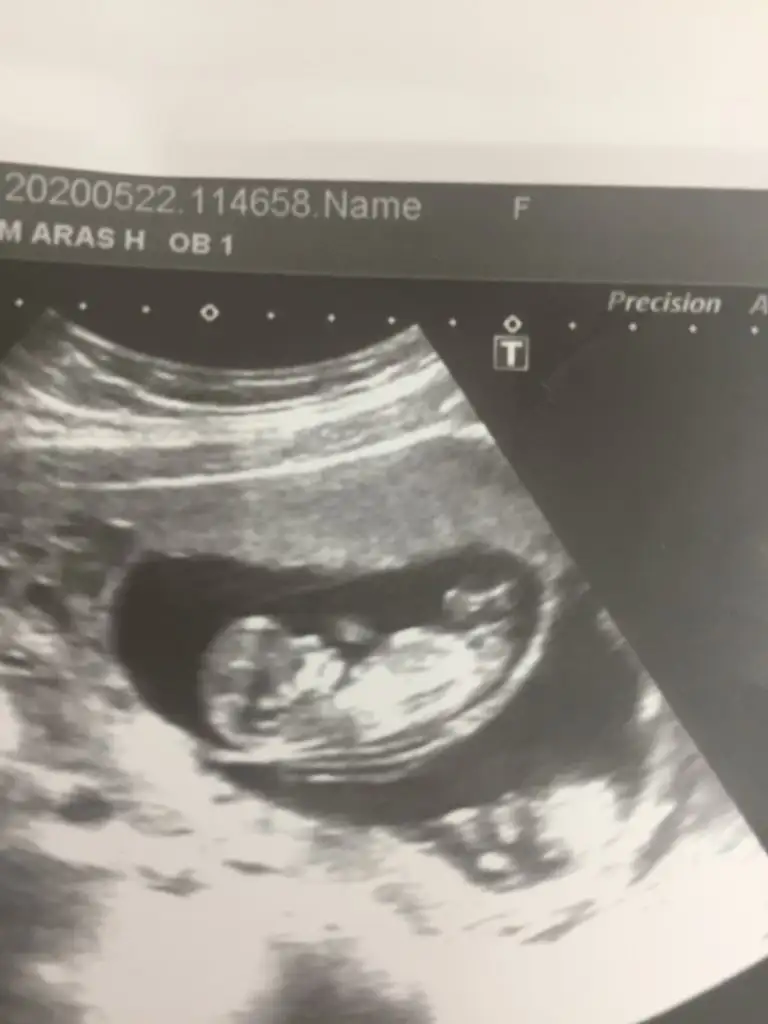

Karından ise erkekCanım banada tahminde bulunabilir misin cok kücük ama cok merak ediyorum ilk hamileiğim5+6 haftalık hamileyim

Evet canım karından , tamam paylaşırımKarından ise erkeken iyi 11 2 13nub usg paylaşım

Kaç haftalık 11 12 13 hafta olmalı sanki buyuk usg tekrar usg paylaşırsınız sanki kız gibi